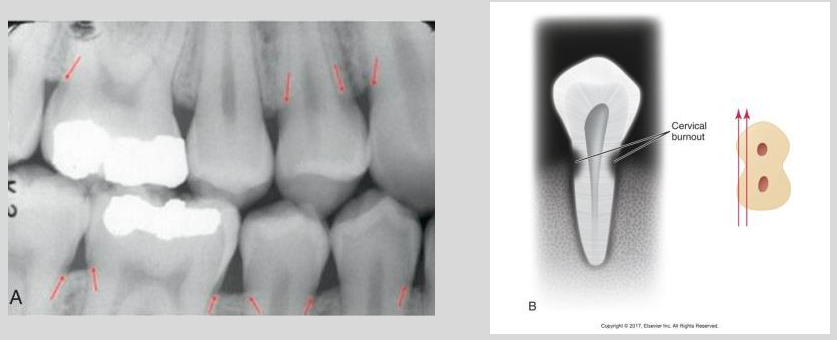

Describe cervical burnout.

Appears as a collar or ill-defined wedge shaped radiolucency on the mesial and distal root surfaces near CEJ

May confuse with root cariesÂ

Artifact results from difference in densities of adjacent tissues

Cervical burnout on posterior teeth

Not to be confused with posterior teeth root cariesÂ